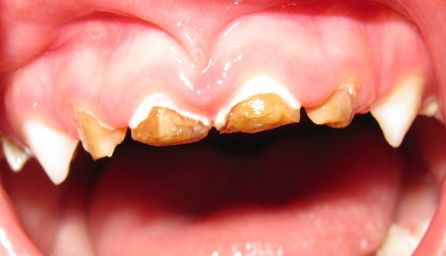

- MANEJO DE LA CARIES DE LA INFANCIA TEMPRANA

Esta es una de las problemáticas de salud pública que de manera desafortunada no tiene programas de atención de amplia cobertura por la complejidad de su manejo integral.

Los pacientes que son afectados por esta entidad siempre son de difícil manejo, tanto en lo comportamental como en la dificultad propia de la rehabilitación necesaria para cada caso especial.

MASIVAS DESTRUCCIONES DE LAS CORONAS DENTALES POR CARIES EN LA DENTICION TEMPORAL.

Esta entidad requiere siempre tratamiento direccionado y ejecutado por especialista en Odontología Pediátrica, cuya formación y experiencia permitan desarrollar los cambios en el contexto familiar y la eliminación de focos sépticos y rehabilitación correspondiente necesaria en estos pacientes.